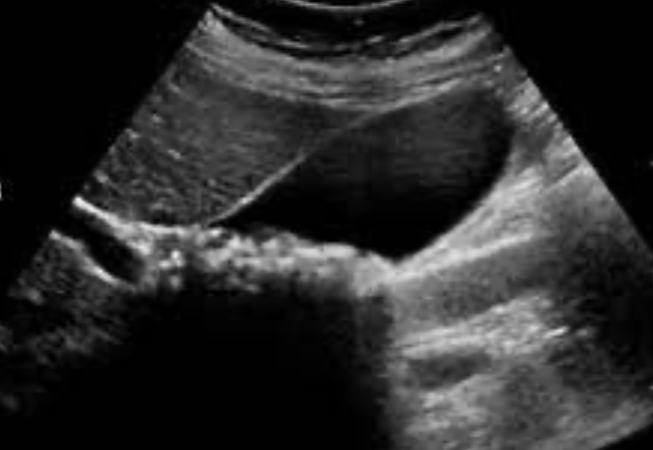

1- What is your diagnosis?

Chronic calcular cholecystitis.

2- Give 4 complications? -

- Pancreatitis. -

- Obstructive jaundice. -

- Gall bladder cancer. -

- Cholangitis

Gallbladder stone (calcular cholecystitis)

Complication:

- cholangitis,

- choledocholithiasis,

- pancreatitis,

- gallbladder perforation

Imaging technique:

- ultrasound